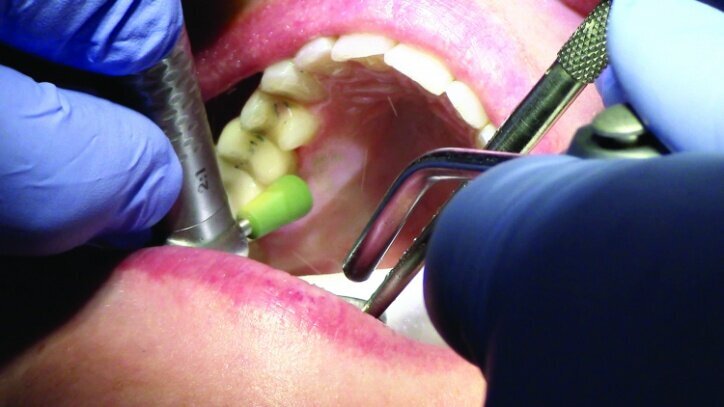

Local anesthesia was achieved with 1.7 cc 2 per cent Lidocaine with 1:100,000 epi, buffered with Onset sodium bicarbonate inj., 8.4 per cent, USP neutralizing additive solution.

Depth guide cuts were made using a 330 bur, which has a 2 mm cutting surface (Figs. 2a–3b). This ensures 2 mm of occlusal reduction to accommodate 2 mm of material thickness on the occlusal surface of the restoration.